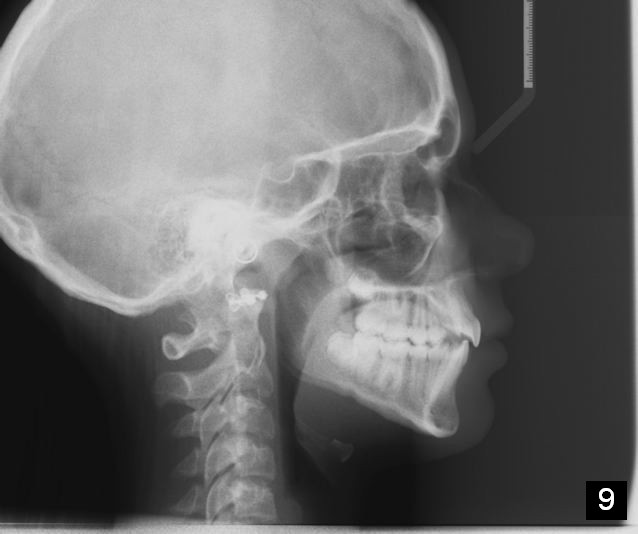

Unilateral Class II Malocclusion

The upper dental midline deviates to the left (Fig.2,4). Facial profile is normal (Fig.3). The right molar relationship is Class II (Fig.5), while the left one is normal or slightly Class III (Fig.6). How to treat?